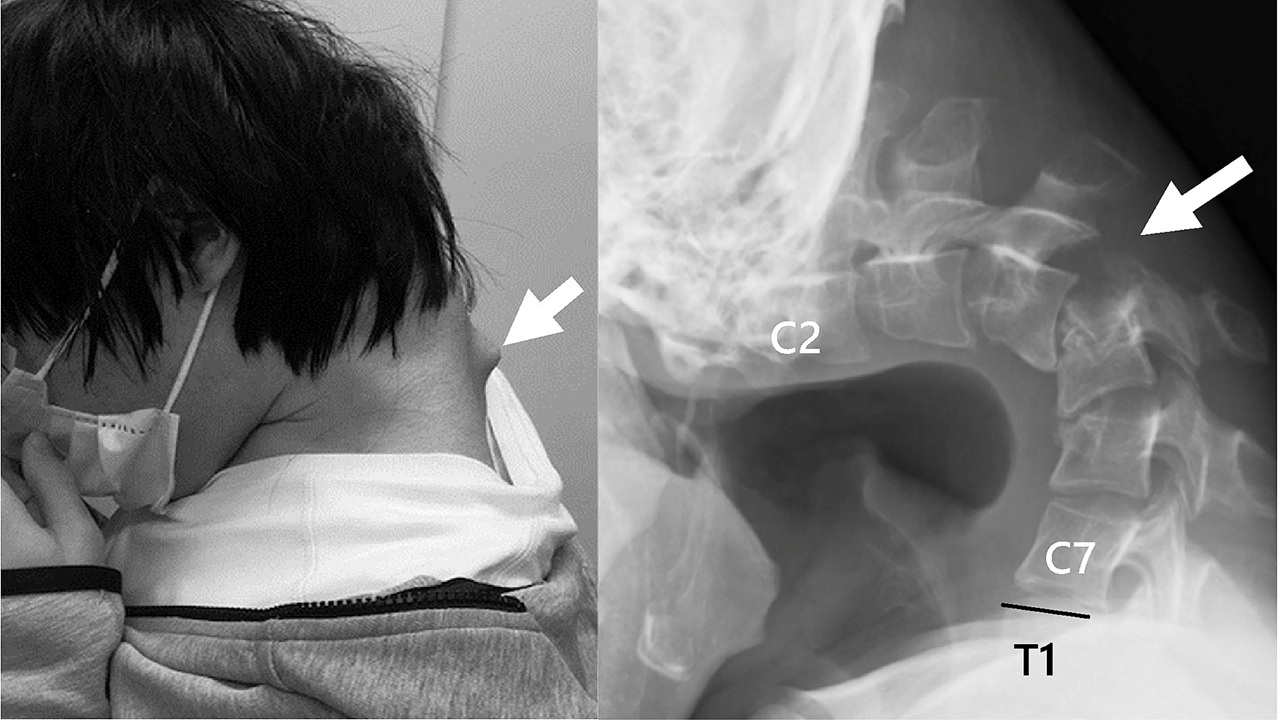

In Giappone, un ragazzo ha dovuto subire un importante intervento chirurgico alla colonna vertebrale a causa di un utilizzo eccessivo dello smartphone per giocare. In particolare, i medici hanno corretto la cosiddetta “sindrome della testa bassa”